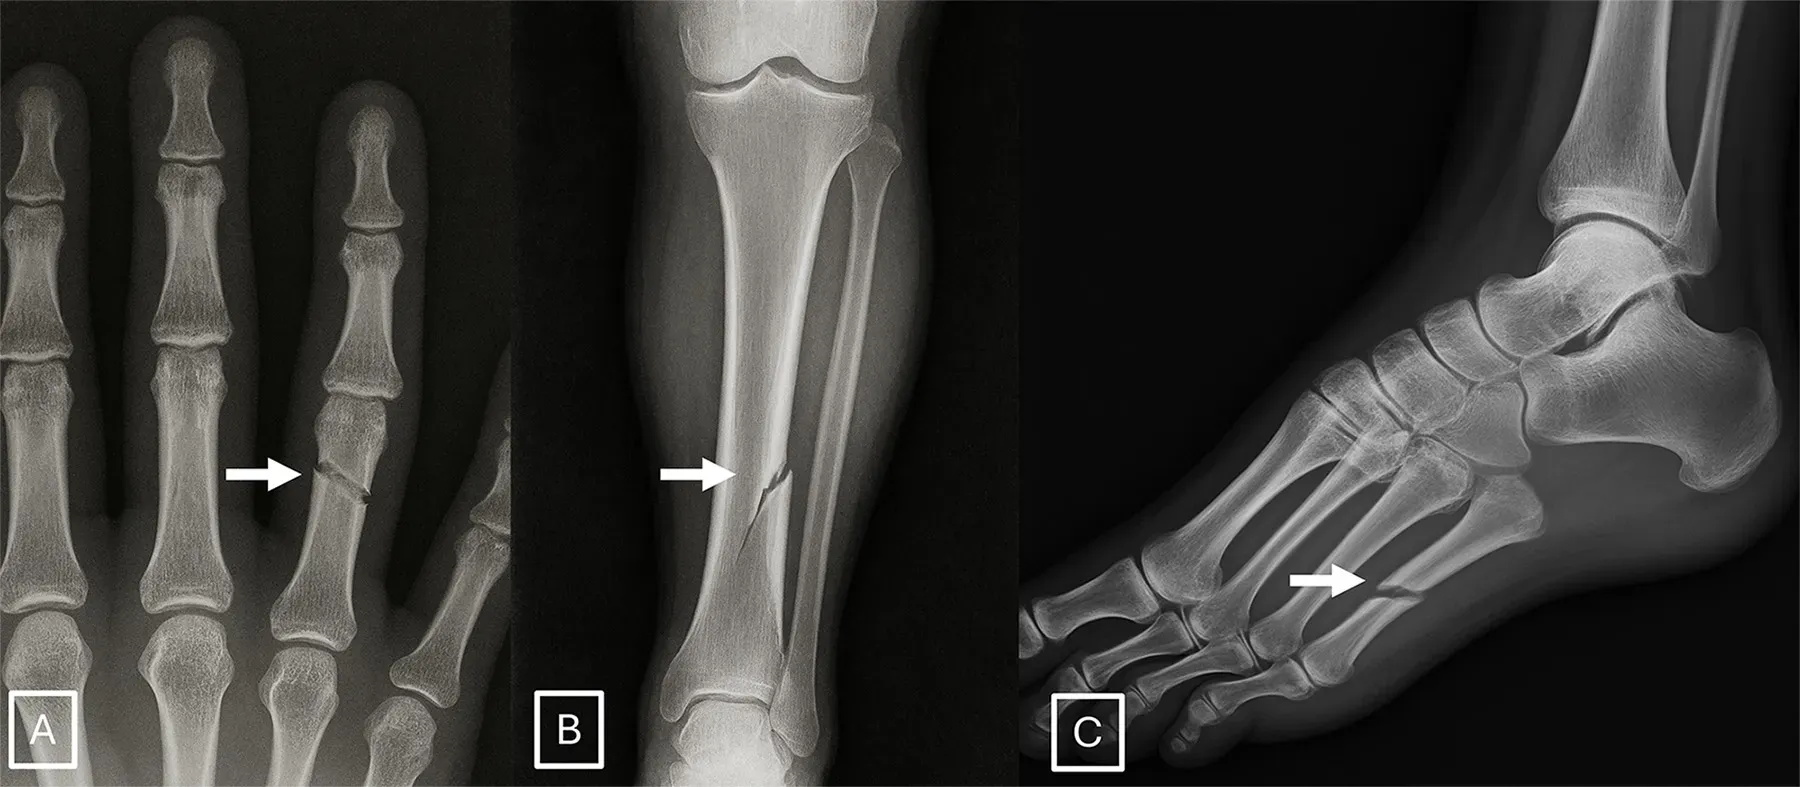

- 骨頭表面過於平滑:真實嘅骨骼邊緣通常會有自然嘅微小凹凸或不規則特徵(例如腰椎嘅 Schmorl 結節)。而 AI 畫出嚟嘅骨頭,皮質骨厚度往往均勻得唔自然,骨折線亦經常顯得太乾淨、太平滑,甚至只係出現單邊皮質骨折斷嘅不合理情況。

- 軟組織細節缺失或唔自然:AI 有時會忽略咗一啲微小但必要嘅解剖細節,例如手部 X 光片入面會無端端缺少咗指甲床嘅陰影,或者植入嘅醫療金屬器材邊緣異常鋒利。